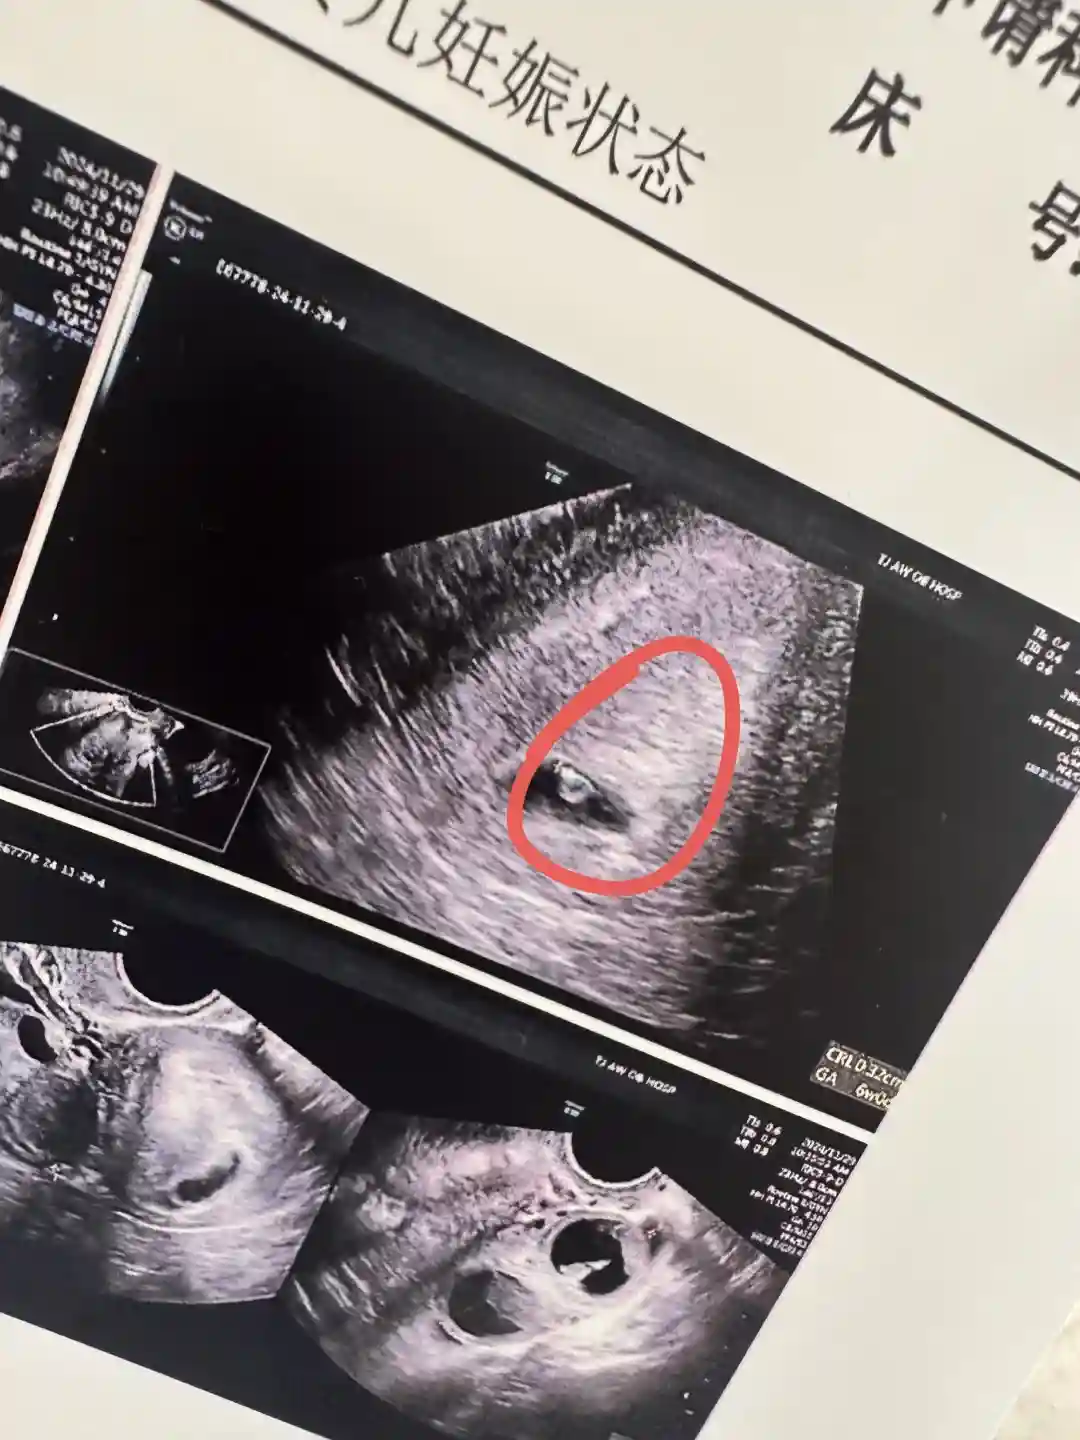

我的试管崽崽8周了